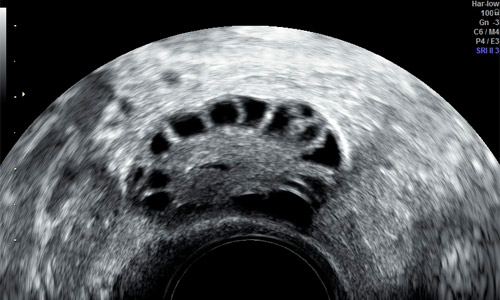

Visión del ovario en edad fértil por ecografía